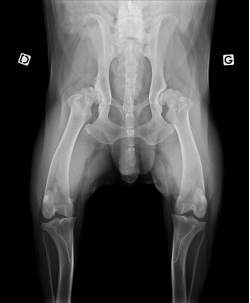

La radiographie est l’un des outils utiles en imagerie médicale. Chez les animaux, comme chez les humains, les radiographies permettent de visualiser certaines parties du corps comme le cœur, les poumons, les intestins ou encore les os.

La plupart des radiographies peuvent être réalisées rapidement mais d’autres nécessitent des tranquillisations de courtes durées car votre animal ne doit pas bouger. On distingue les utilisations suivantes de l’appareil radiologique :

- Radiographies des membres : pour la recherche de fractures mais également l’évaluation de différents problèmes articulaires comme l’arthrose ou la dysplasie.

Appareil de radiographie

Nous disposons d’un équipement de radiographie numérique, permettant d’avoir des clichés de votre animal en quelques minutes.

Les radiographies sont d’un atout majeur dans le diagnostic de nombreuses pathologies (fractures, problèmes respiratoires, troubles digestifs …).